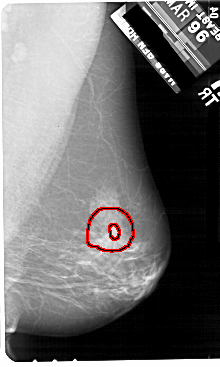

A_1908_1.LEFT_MLO

LEFT_MLO LINES 5491 PIXELS_PER_LINE 3511 BITS_PER_PIXEL 12 RESOLUTION 43.5 NON_OVERLAY

RIGHT_MLO LINES 5491 PIXELS_PER_LINE 3286 BITS_PER_PIXEL 12 RESOLUTION 43.5 OVERLAY

FILE: A_1908_1.RIGHT_MLO.OVERLAY

TOTAL_ABNORMALITIES 1

ABNORMALITY 1

LESION_TYPE MASS SHAPE IRREGULAR MARGINS SPICULATED

ASSESSMENT 5

SUBTLETY 4

PATHOLOGY MALIGNANT

TOTAL_OUTLINES 2

BOUNDARY

CORE